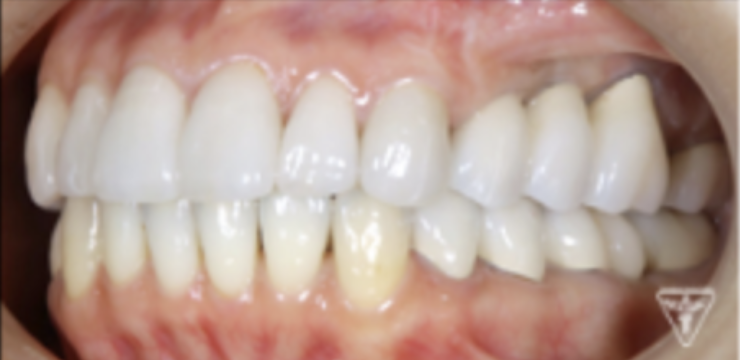

最終補綴物装着時

咬合調整

粉砕効率の高い小さな点による均衝接触をつくります。

咬合様式は、ミューチャリープロテクトオクルージョンを付与しました。